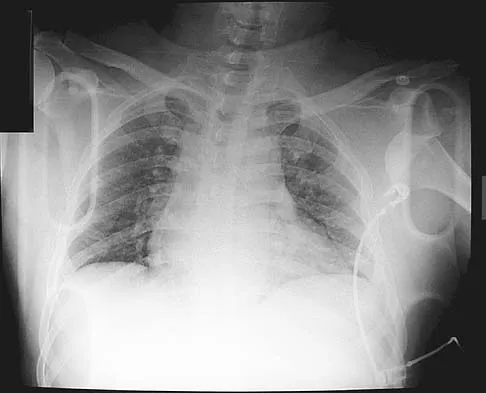

Which of the following findings is seen in the chest radiograph shown in Figure 13?

Explanation